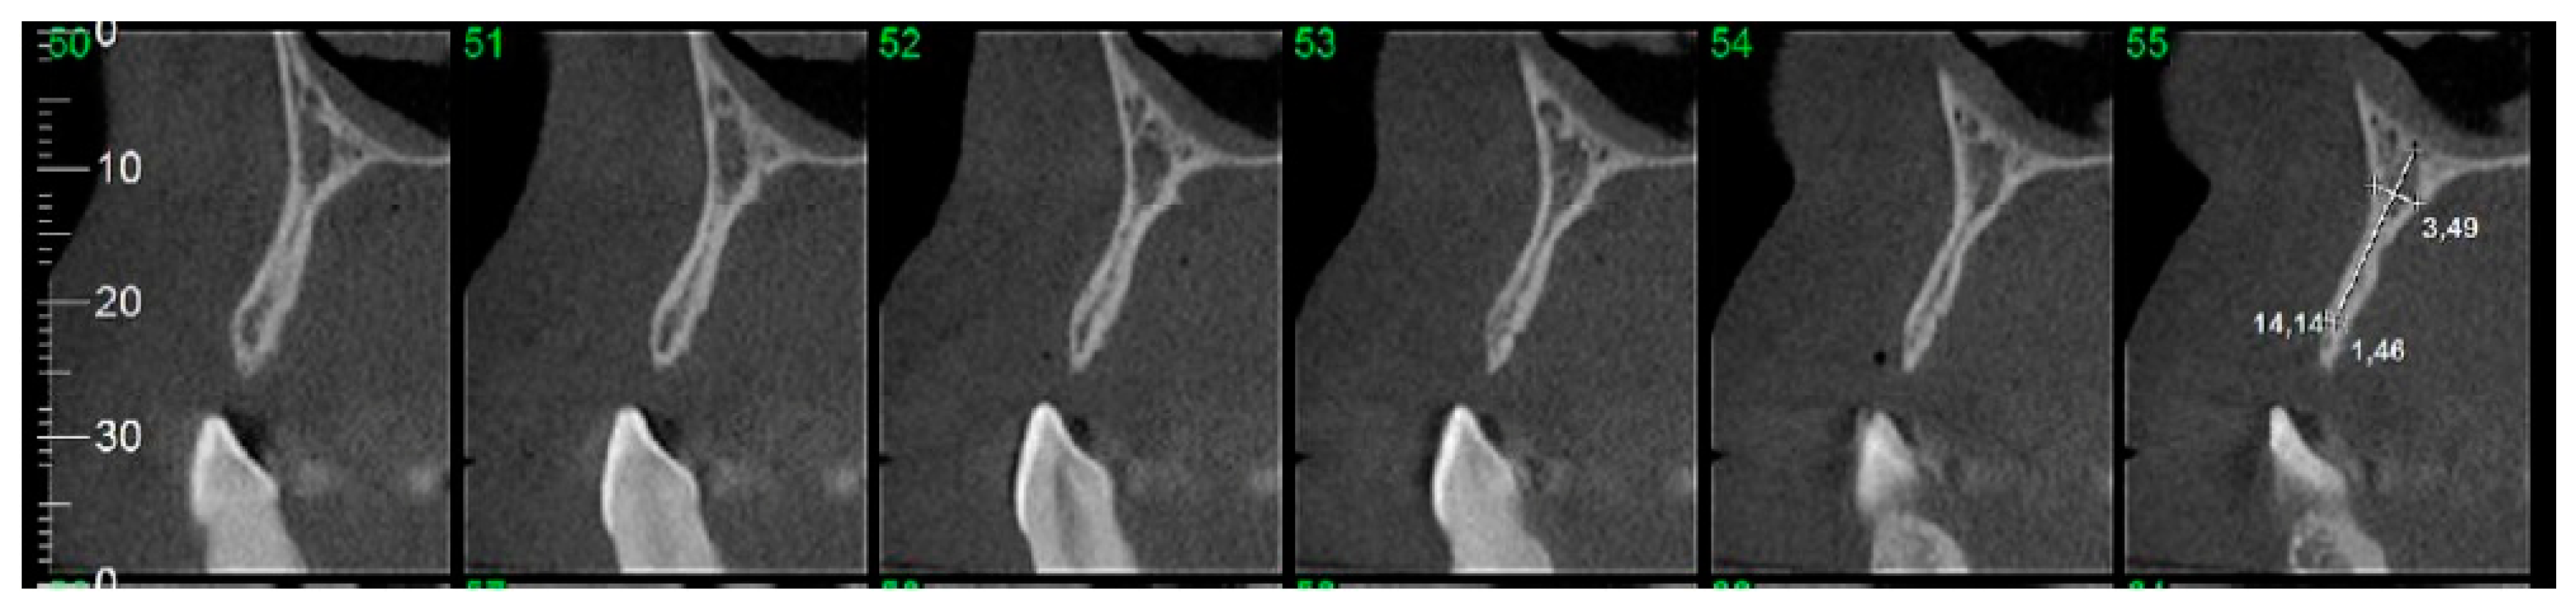

2.7. Computed Tomographic (CT) Evaluation